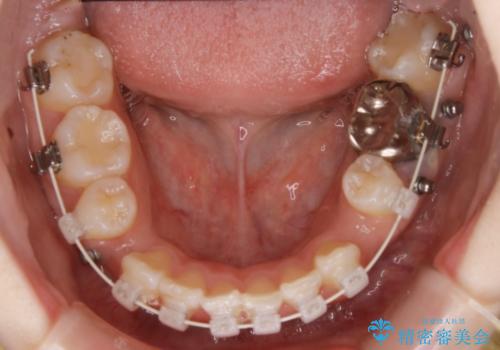

ハーフリンガル装置

ワイヤー矯正の中でも、上顎を裏側・下顎を表側に装置をつけて動かす方法をハーフリンガルといいます。

ハーフリンガルを選択すると、ワイヤー矯正の利点である抜歯ケースへの対応が可能な点と、表側の装置の欠点である装置が目立つという点をカバーして矯正治療を進めることができます。

表側の装置と違い、使えるワイヤーの種類に制限があり平均治療期間が長くなりやすい点、装置の作製自体の金額が掛かることから費用面で表側装置よりも高額になるという点はマイナスポイントであるといえますが、しっかりと口元を下げたり、噛み合わせの構築を行うことは遜色なく行えるため人気のある装置となっております。

また、裏側に装置が付くことによって喋り辛さを感じる方もいらっしゃいます。